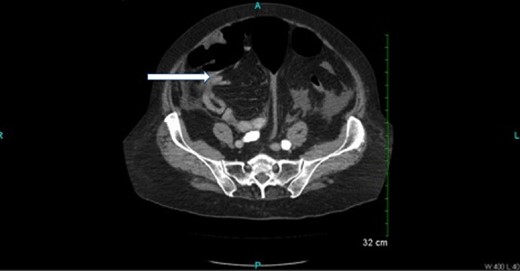

CT scan (Figs 2 and 3) revealed a large hematoma at the lateral margin of the spleen that displaced the spleen medially and compresses its lateral margin. A moderate amount of relatively low attenuation fluid also tracked into the right paracolic gutter and perihepatic space. There also appeared to be a 3.5 × 2.5 cm broad-based mass along the wall of the right colon. The CT scan of the chest also demonstrated a pulmonary embolus in a subsegmental artery of the right upper lobe. Given these findings, the patient was aggressively resuscitated with packed red blood cells and taken emergently to the operating theatre.

Oral and intravenous contrast enhanced CT of the abdomen demonstrating air within the colonic lumen and a 3.5 × 2.5 cm broad-based mass along the wall of the right colon (white arrow).